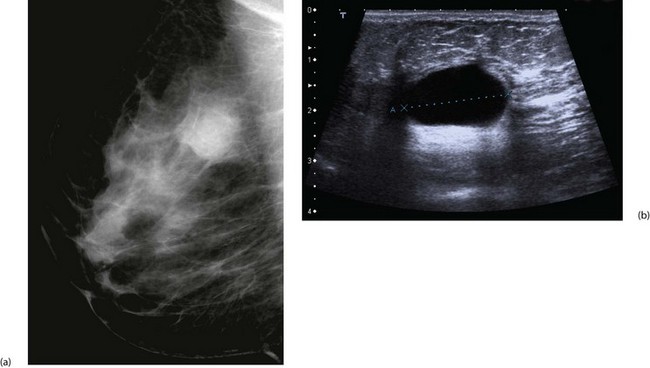

Cyst formation is more prevalent over the age of 40 years and in perimenopausal women. Cysts may present symptomatically as single or occasionally multiple lumps. Cysts develop from lobules and are fluid-filled spaces. Microcysts are part of the involutionary process and may coalesce to produce a larger cyst which presents as a smooth, round palpable lump. Larger cysts may be tense, tender and fluctuant with the texture of a table tennis ball. Cysts can usually be diagnosed clinically and are readily confirmed with ultrasonography; they are usually recognisable on a mammogram. Simple cysts can be aspirated under ultrasound control or freehand. Provided the cyst fluid is not blood-stained, there is no residual lump post aspiration and there are no sonographically suspicious features, patients can be discharged without further follow-up, although cysts can recur or new cysts develop (see Fig. 45.21). Cysts are uncommon over the age of 60 years unless the patient is taking HRT. Under these circumstances it is important to exclude an intracystic papilloma, intracystic carcinoma or a cystic carcinoma.